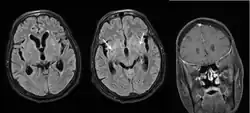

Diagnosis is by isolating Cryptococcus from a sample of affected tissue or direct observation of the fungus by using staining of body fluids.[9] It can be cultured from a cerebrospinal fluid, sputum, and skin biopsy.[9] Characteristic neuroimaging findings include dilated Virchow-Robin spaces, the ‘dirty CSF sign’,[15] hydrocephalus, cryptococcomas and hazy brain base sign. Many of these findings are non-specific, but the presence of basal meningeal enhancement is significant as it is associated with the future development of cerebral infarct. Treatment is with fluconazole or amphotericin B.[9][10]

Increased intracranial pressure is seen in about 50% of those with HIV-associated cryptococcal meningitis and is usually associated with a high fungal burden. Regular (often daily) lumbar punctures to lower the intracranial pressure by draining CSF is associated with reduced mortality in those with cryptococcal meningitis (with or without HIV).[19][49][11] But in those with suspicion of non-communicating hydrocephalus (which may present as focal neurologic symptoms or impaired mentation), a CT or MRI of the brain is required before lumbar puncture to rule out hydrocephalus, due to the risk of brain herniation with lumbar puncture. Non-communicating hydrocephalus is rare in those with HIV-associated cryptococcal meningitis.[19]